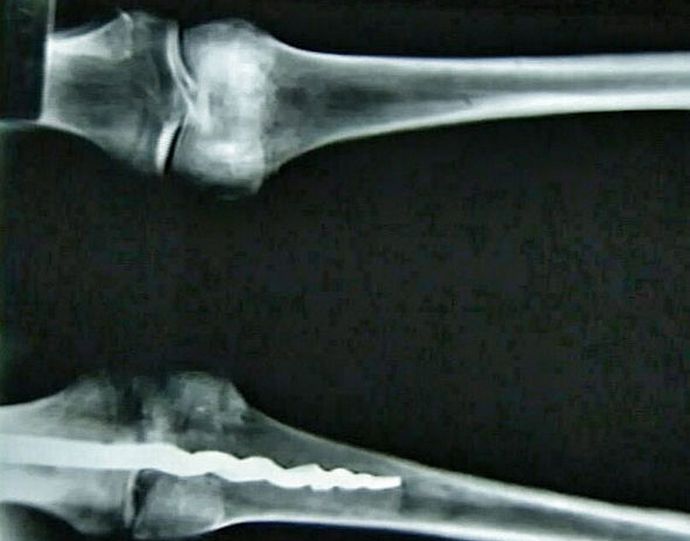

Fotografija grupa otvorenih izvora koja sprovode američki istraživači DNK analiza egipatske mumije pronašla je u njenom tijelu pravu ortopedska igla, koja nije lošija u dizajnu moderni pandan. Jedinstvena dužina pronalaska 23 centimetara, izradila je od metala, a dizajn joj je drugačiji upečatljiva je s ortopedskim iglicama koje se koriste u njima medicina danas.

Prema stručnjacima, u kolenu čovjeka su drevni kirurzi stavite osovinicu koja učvršćuje kosti i osigurajte je organska smola. To su učinili tako vješto i profesionalno, da i najsloženija operacija nije ostavila traga na pacijentovom telu. Sudeći prema otkrivenom nalazu, metodama, koriste je ljekari u savremenoj medicini odavno poznati našim precima i uspješno ih primjenjuju u praksi.

Još uvijek nije poznato ko je tačno bio Egipćanin, u kolenu koja je otkrivena neverovatna igla. Naučnici iz Amerike Univerzitet Brigham Young vidio ga je sasvim slučajno rendgenski zrak, a potom uklonjen iz tijela, malo iznenađen njegovo otkriće.

Pronađena mumija nije stara manje od 3000 godina, što znači da i tada stari Egipćani imali su potrebno znanje da konstruiraju igle koje mogu ispraviti ispravljene kosti položaja i provođenja složenih hirurških operacija.

Naučnici još ne mogu objasniti prirodu misterioznog nalaza, okrenuli su svoje ideje o drevnoj medicini. Wilfred Griggs, vodeći istraživačku grupu, u čijim se rukama pokazalo jedinstvena mama, uvjerena da neće dati mnogo ni jednoj saznajte tačno kako su egipatski ljekari uspjeli stvoriti i smjestiti u njih čovjekovo tijelo je takav moderni pin.